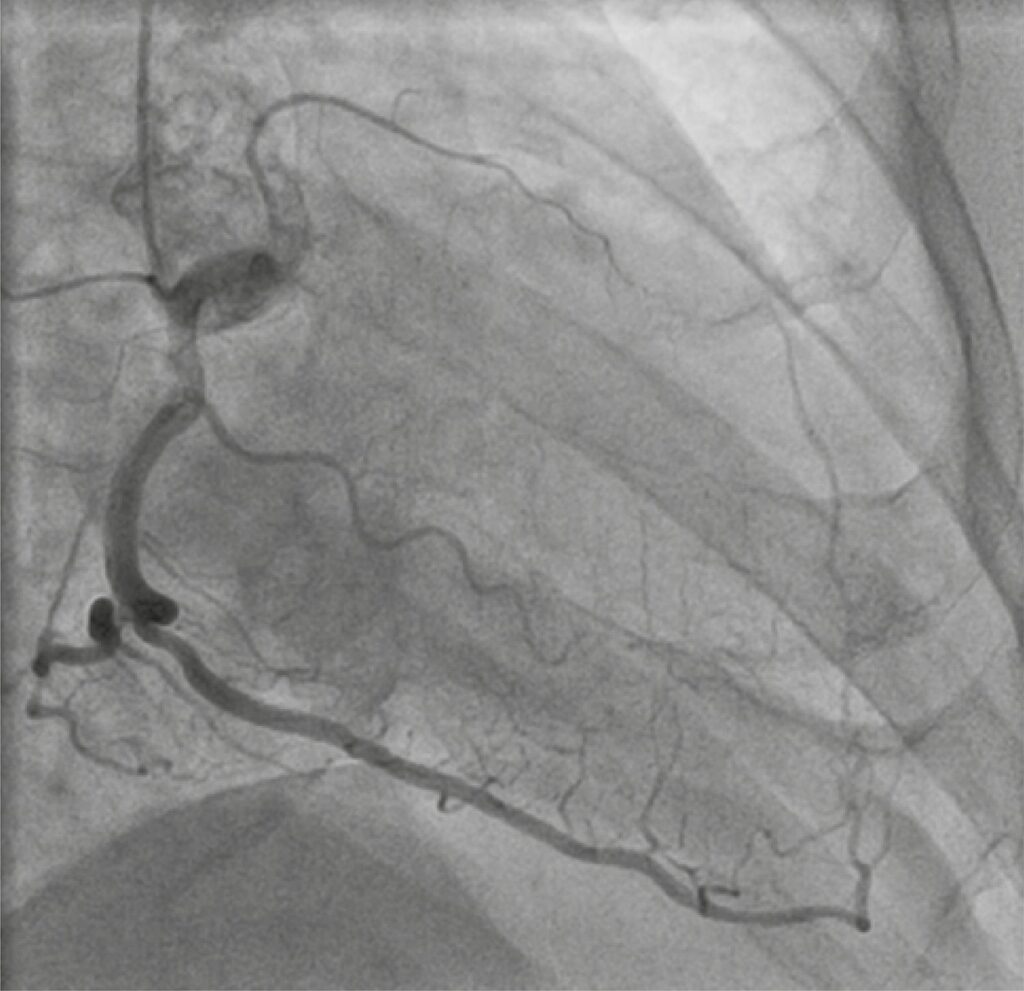

A 67-year-old man with several cardiovascular risk factors was referred to cardiology consultation, due to effort angina – Canadian Cardiology Society (CCS) class II/IV, for the last 6 months, under optimal medical treatment. Resting electrocardiogram and transthoracic echocardiogram (TTE) were normal. Stress treadmill test was positive. The coronary angiogram revealed a long proximal chronic total occlusion (CTO) of the left anterior descending artery (LAD; J-CTO=1, Rentrop3), a distal CTO of the left circumflex artery (J-CTO=0, Rentrop3) and a 50% stenosis in the posterolateral branch (SYNTAX score 21).

Considering symptoms, angiographic findings, and patient preference, a percutaneous coronary intervention (PCI) of LAD was planned, as priority, and performed using bi-radial access, contralateral injection, and anterograde wire escalation approach ( ). Sion guidewire was advanced to distal LAD with the aid of FineCross microcatheter . Two overlapping everolimus-eluting stents (2.5x48mm and 3x23mm) were deployed in proximal LAD, after adequately pre-dilatation. Immediately after post-dilatation with non-compliant balloon (3x23mm) at 22atm, the patient developed a severe Ellis type III perforation in the mid LAD (). The post-dilatation balloon was re-inflated at 8atm, at the site of perforation to stop bleeding. A bedside TTE was performed and revealed small circumferential pericardial effusion without hemodynamic impact.